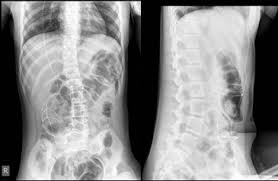

Hydrocephalus Dr Ng Neuroedu